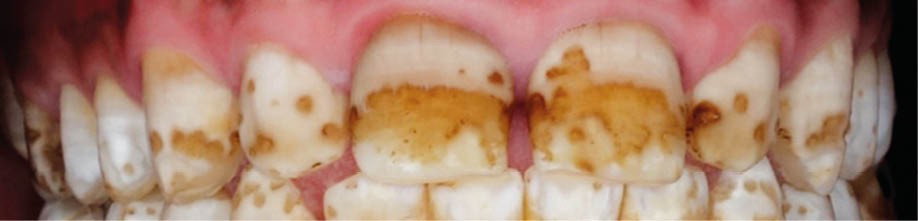

L’émail dentaire, tissu le plus dur et le plus minéralisé du corps humain, peut être affecté par des anomalies génétiques inscrites dans le génome de l’individu, mais également par des facteurs environnementaux. Ces facteurs sont multiples et signent un événement ou une exposition à un xénobiotique au cours de la vie de l’individu. Parmi les atteintes développementales acquises de l’émail, outre la fluorose, figurent les hypominéralisations à type de MIH (Molar Incisor Hypomineralization). Celles-ci sont observées de manière caractéristique sur une ou plusieurs premières molaires permanentes et potentiellement les incisives permanentes éruptant vers l’âge de 6 à 7 ans d’après la description qui en a été faite en 2001 [3] (fig. 1 à 3). La prévalence est importante, la MIH touchant, selon les méta-analyses les plus récentes, plus de 13 % des individus dans le monde, et peut varier selon les études et les pays dans lesquels elles sont menées [4, 5]. Son étiologie est encore incertaine, mais la communauté scientifique s’accorde sur le fait qu’elle serait multifactorielle et notamment en lien avec la survenue d’une hypoxie à la naissance, de fortes fièvres, des épisodes infectieux de la sphère ORL dans la petite enfance ou encore avec une prédisposition génétique [6]. Cette pathologie aurait toujours existé, mais sa prévalence semble être en nette augmentation. Peu d’études ont été réalisées sur cette évolution dans le temps [7].

Les leviers à activer dès maintenant pour répondre aux enjeux de santé publique liés à la MIH sont nombreux. C’est d’abord le développement de la collaboration avec les professionnels de santé de la petite enfance. Ceux-ci, dont les médecins généralistes, doivent être sensibilisés au tableau clinique de la MIH – différent de celui de la fluorose ou de l’amélogenèse imparfaite par son caractère asymétrique et sa localisation préférentielle aux molaires et incisives permanentes – afin de favoriser son dépistage et sa prise en charge précoce.

Les enjeux sont très importants. On constate néanmoins que cette maladie est encore mal connue, même des chirurgiens-dentistes. Pour le seul diagnostic, elle est souvent confondue avec la fluorose ou une mauvaise hygiène bucco-dentaire*.